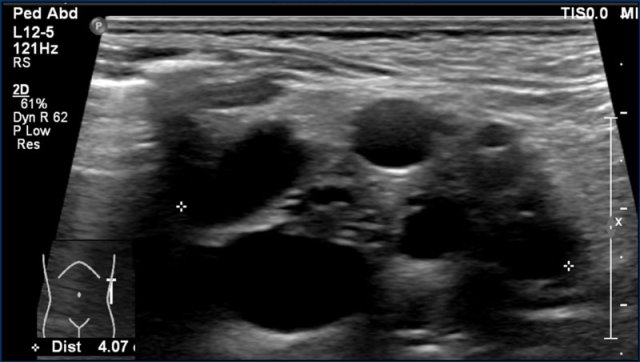

Multicystic dysplastic kidney

An 8-months-old boy with a multicystic dysplastic kidney.

On ultrasound multiple cysts are present and no normal renal tissue is seen.

No additional imaging is needed.

Often follow-up ultrasound is performed to ascertain regression of the MCDK over time and to diagnose contralateral abnormalities (in 30% of cases).